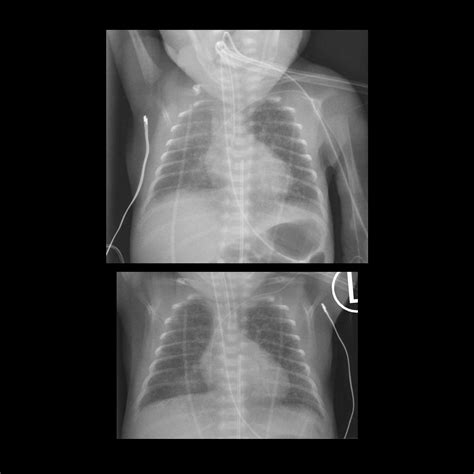

• X-rays: Often the first line of defense for bone fractures or lung issues.

X-ray Minimal Bone fractures, pneumonia, chest congestion